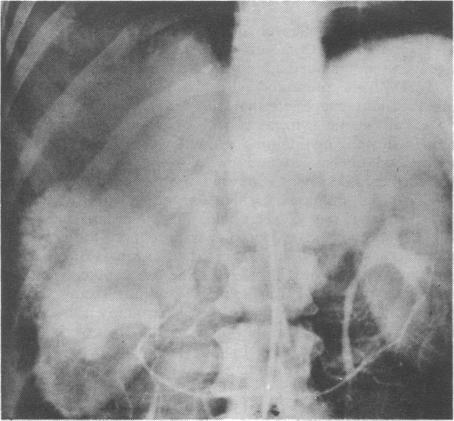

Three cases are reported of tumour-like lesions of the liver in women who had been on oral contraceptives for long periods. These malformations have a prominent vascular component and may present with haemoperitoneum and shock. The possibility of an association between liver hamartomas and oral contraceptive therapy has to be considered.

报告了3例长期服用口服避孕药的女性肝脏肿瘤样病变。这些畸形有显著的血管成分,可能表现为腹腔积血和休克。必须考虑肝错构瘤与口服避孕药治疗之间存在关联的可能性。